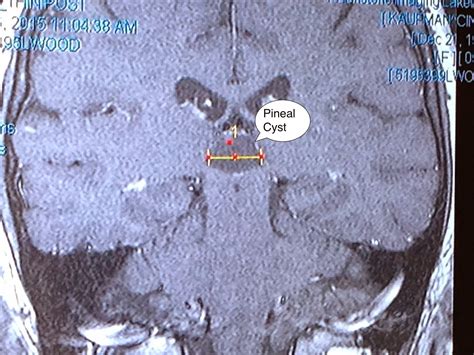

Diagnosing and Monitoring

In most instances, a Pineal Gland Cyst is discovered incidentally. Once identified, neuroradiologists evaluate the cyst using magnetic resonance imaging (MRI). The imaging helps determine the size, appearance, and whether the cyst is putting pressure on critical brain structures.

Size Most are smaller than 1 cm (often classified as "incidentaloma").

Appearance Smooth, thin-walled, and fluid-filled.

Growth Typically stable; they rarely grow or change over time.

Management Observation via follow-up MRI is the standard approach for small cysts.

If the radiologist notes that the cyst has "benign features," the medical recommendation is usually a wait-and-see approach. This means your doctor may schedule a follow-up MRI in six to twelve months to ensure the cyst has not changed in size or shape. This proactive monitoring provides peace of mind while avoiding unnecessary procedures.

• pineal gland cyst mri

• pineal gland cyst radiology

• pineal cyst size chart